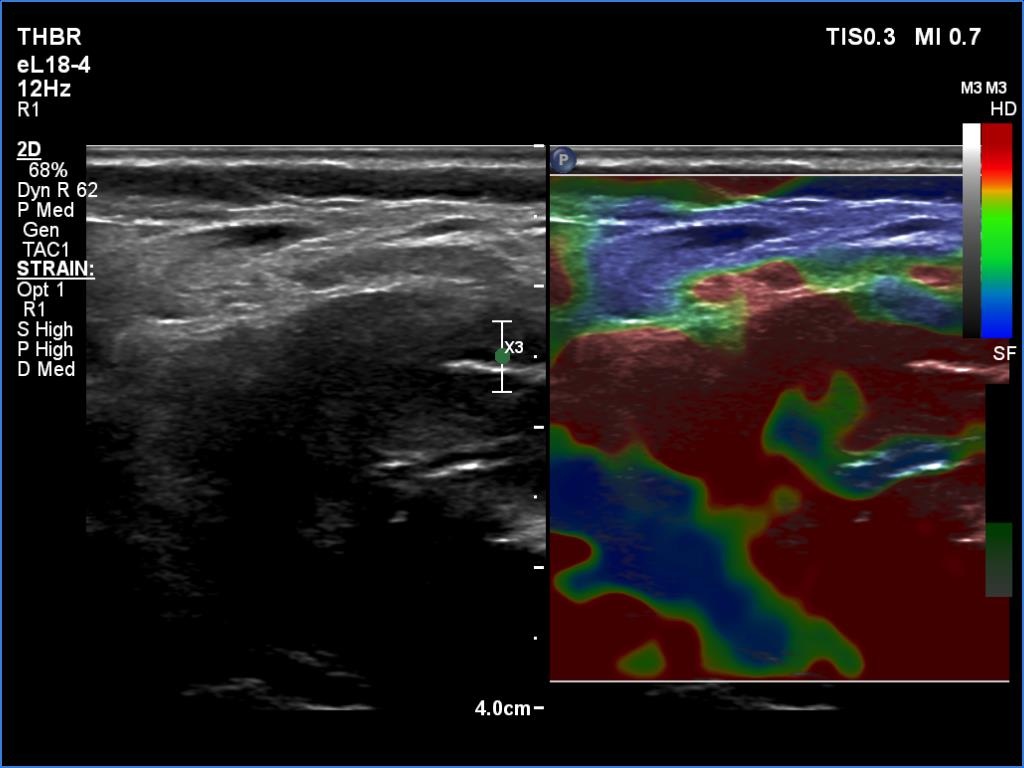

Thyroid cancers - case 1174 (ultrasonographic picture 10)

Right lobe, transverse view, elastography. The nodule has very hard areas.